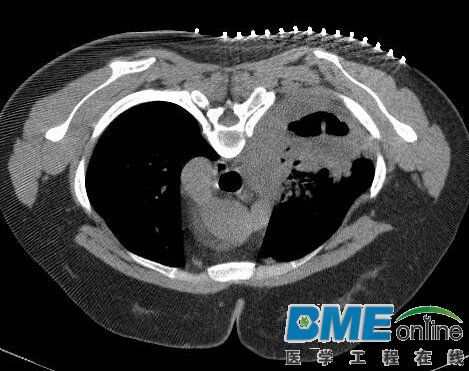

很多病人需要做微创穿刺介入手术,需要进行病灶点的体表定位,传统医生会自制简单的工具,不清晰不方便不准确,可以看看图片中的方法进行需要的可联系 周先生 13626259623(电话和微信)

CT下定位,介入穿刺穿刺定位,肿瘤消融定位,医用定位纸,显影胶带,可以快速准确定位病灶点的体表位置,然后进行穿刺.